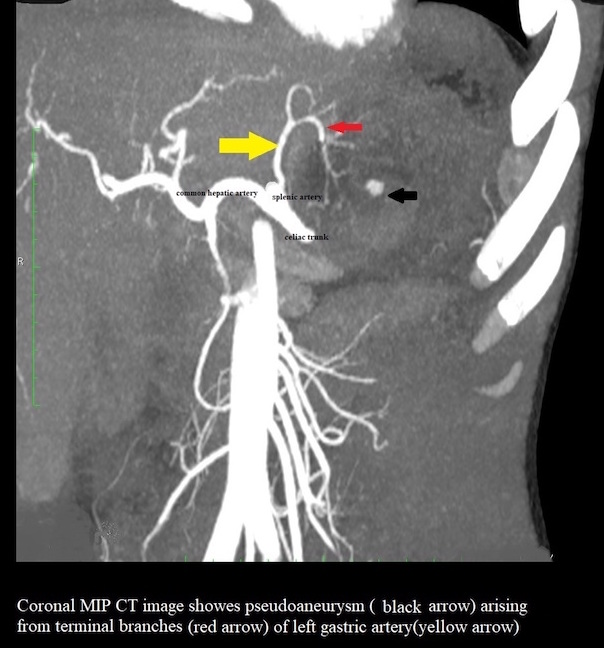

A well-defined oval cyst isseen abutting the pancreatic body and tail, suggestive of a pancreatic pseudocyst. The pancreatic duct is minimally prominent. Thecyst is seen anteriorly abutting the stomach wall with resultant diffuse oedematousthickening of the walls of the stomach.A few ill-defined hyperdensitiesare seen within the cyst, suggestive of chronic hemorrhages/ sludge •Atiny nodular well-defined intensely enhancing lesion is seen along the cyst wall anteriorly on arterialphase representing peseudoaneurysm.

- Complications associated with pancreatic pseudocysts include infection, rupture, and hemorrhage. They can erode into adjacent vessels—most commonly the splenic artery—and produce a pseudoaneurysm.

- High-resolution MDCT or MR angiography can depict the pseudoaneurysm as a well-delineated rounded structure originating from the donor artery.